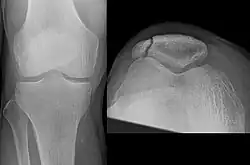

- Comminuted fracture of patella

The patella can break in various ways depending on the way it is injured, and into two or more pieces.[1] Types include transverse, with one fracture line and is the most common type,[5] marginal, osteochondral and the rare vertical type, or stellate, where a direct compression force gives rise to a comminuted pattern.[5][7] Patella fractures can be further classified as displaced, where the broken ends of bone do not line up correctly and separate by more than 2mm, or undisplaced and stable where pieces of bone remain in contact with each other.[1][7] If fragments of patella bone stick out from the skin it is known as an open patella fracture, and closed if the overlying skin is intact.[1]